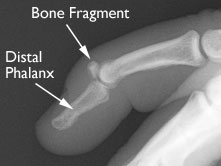

Your doctor will most likely order x-rays of the injury. If a fragment of the distal phalanx was pulled away when the tendon ruptured, or if there is a larger fracture of the bone, it will appear in an x-ray. An x-ray will also show whether the injury pulled the bones of the joint out of alignment.

This x-ray shows that a piece of the distal phalanx bone broke away with the tendon.